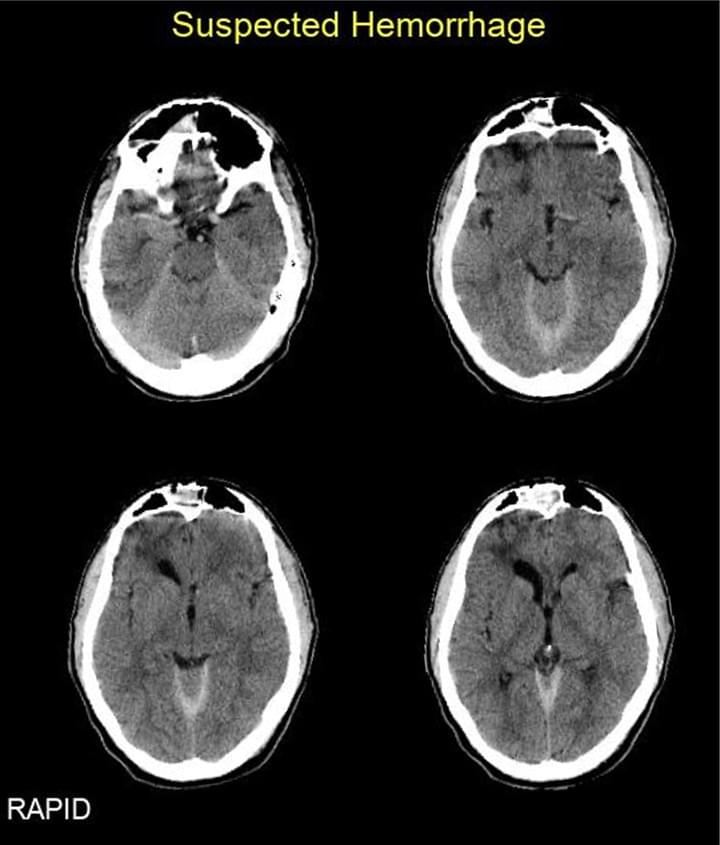

Automated Cerebral Hemorrhage Detection Using RAPID

Heit JJ, et al. (2021) AJNR Jan;42(2):273-278. doi: 10.3174/ajnr.A6926. Epub 2020 Dec 24.